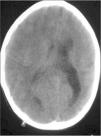

En la tomografía computarizada craneal (TCC) existe una asimetría entre ambos hemisferios cerebrales: el hemisferio izquierdo (HI) es de menor tamaño, con ventrículo lateral (VL) moderadamente dilatado. El hemisferio derecho (HD) sobrepasa la línea media y el VL derecho es de dimensiones normales (fig. 1 y 2).

En la resonancia magnética (RM) craneal se evidencia el mayor tamaño del HD, que presenta un área de mayor brillo en T2 y Flair localizada en la sustancia blanca parietal posterior, mayor tamaño de la región derecha del troncoencéfalo respecto a la izquierda y polimicrogiria en el HI, junto con las alteraciones morfológicas ya visibles en la TCC (fig. 4).